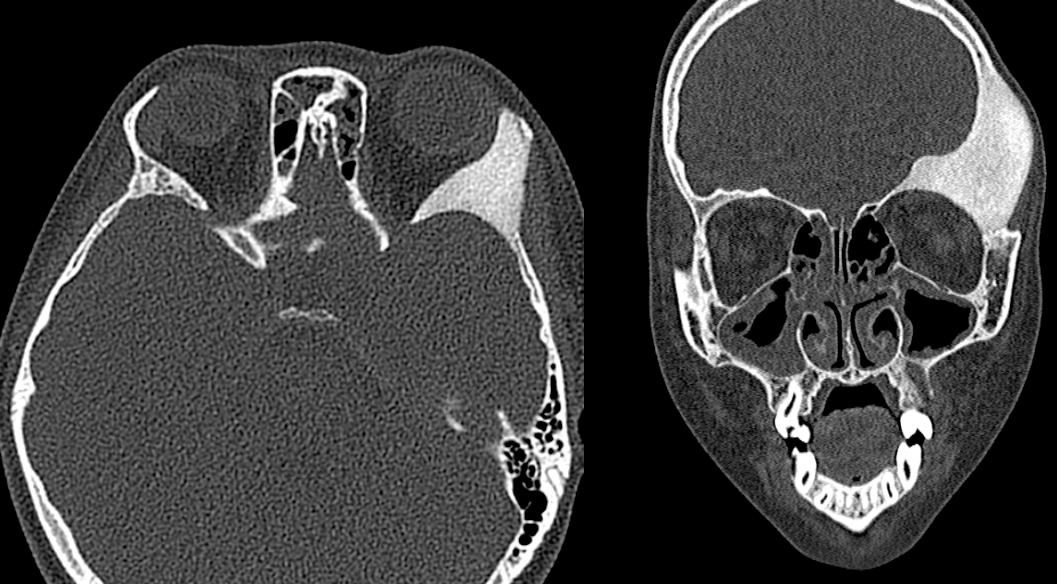

②MRI

病灶内信号变化与病灶内成分相关,T1WI: 通常为等信号,也可为低信号或混杂信号;T2WI: 通常较低,但可能有信号较高的区域或混杂信号区域;T1WI+C(Gd): 呈不均匀增强。

(注:双侧顶骨板障不均匀增厚,T1WI 呈等、低信号,T2WI 呈稍低信号,增强 T1WI 呈轻度不均匀强化。)